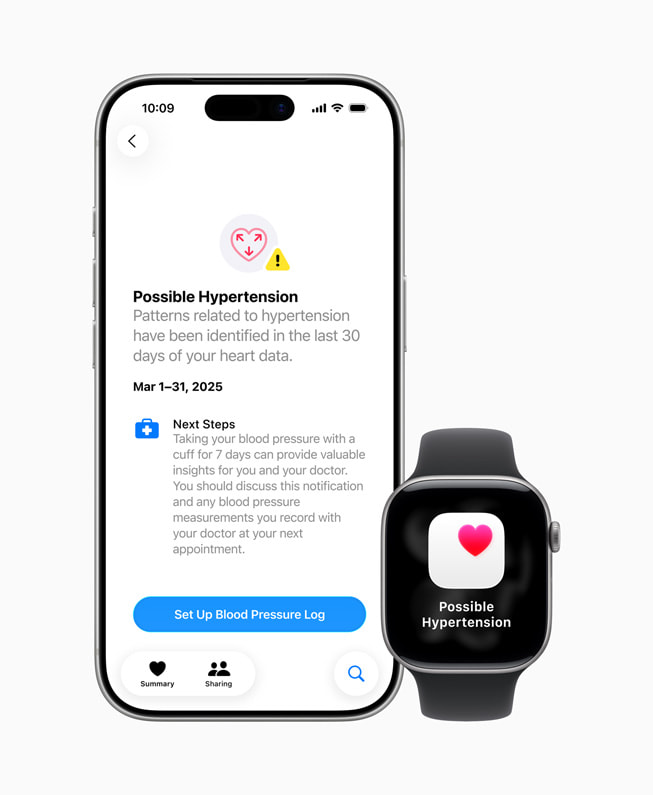

The Apple Watch hypertension detection feature uses the optical heart sensor to analyze blood vessel responses over 30-day periods, analyzing how a user’s blood vessels respond to the beats of the heart. The algorithm works passively in the background reviewing data over 30-day periods, and will notify users if it detects consistent signs of hypertension.

Users who receive notifications are advised to monitor their blood pressure for seven days using a third-party cuff and share results with healthcare providers, following American Heart Association guidelines.